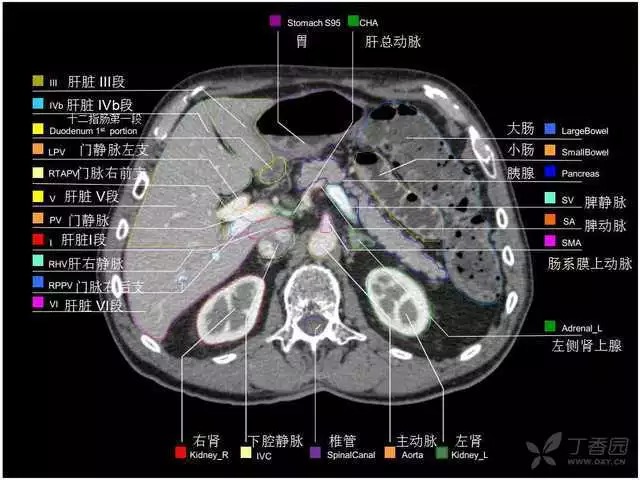

腹部肝脏高清CT断层的图谱

全腹部高清CT图谱,淋巴结彩色图谱,血管解剖图谱大汇总!

超声肝脏分叶及分段

肝脏分段和基本解剖学标志